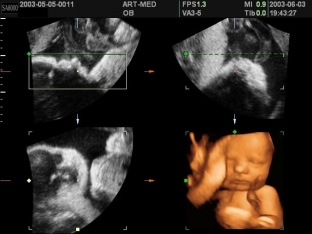

At the background of placental insufficiency due to blood loss and hypoxia, the donor fetus develops hypovolemia, and the recipient fetus suffers from heart failure resulting from hypervolemia. Ultrasound examination makes it possible to diagnose the syndrome of feto-fetal blood transfusion. The specific features of this syndrome are the following echographic data:

- severe polyhydramnios and large bladder with polyuria in the recipient fetus;

- almost complete "absence" bladder and anuria in the donor fetus.